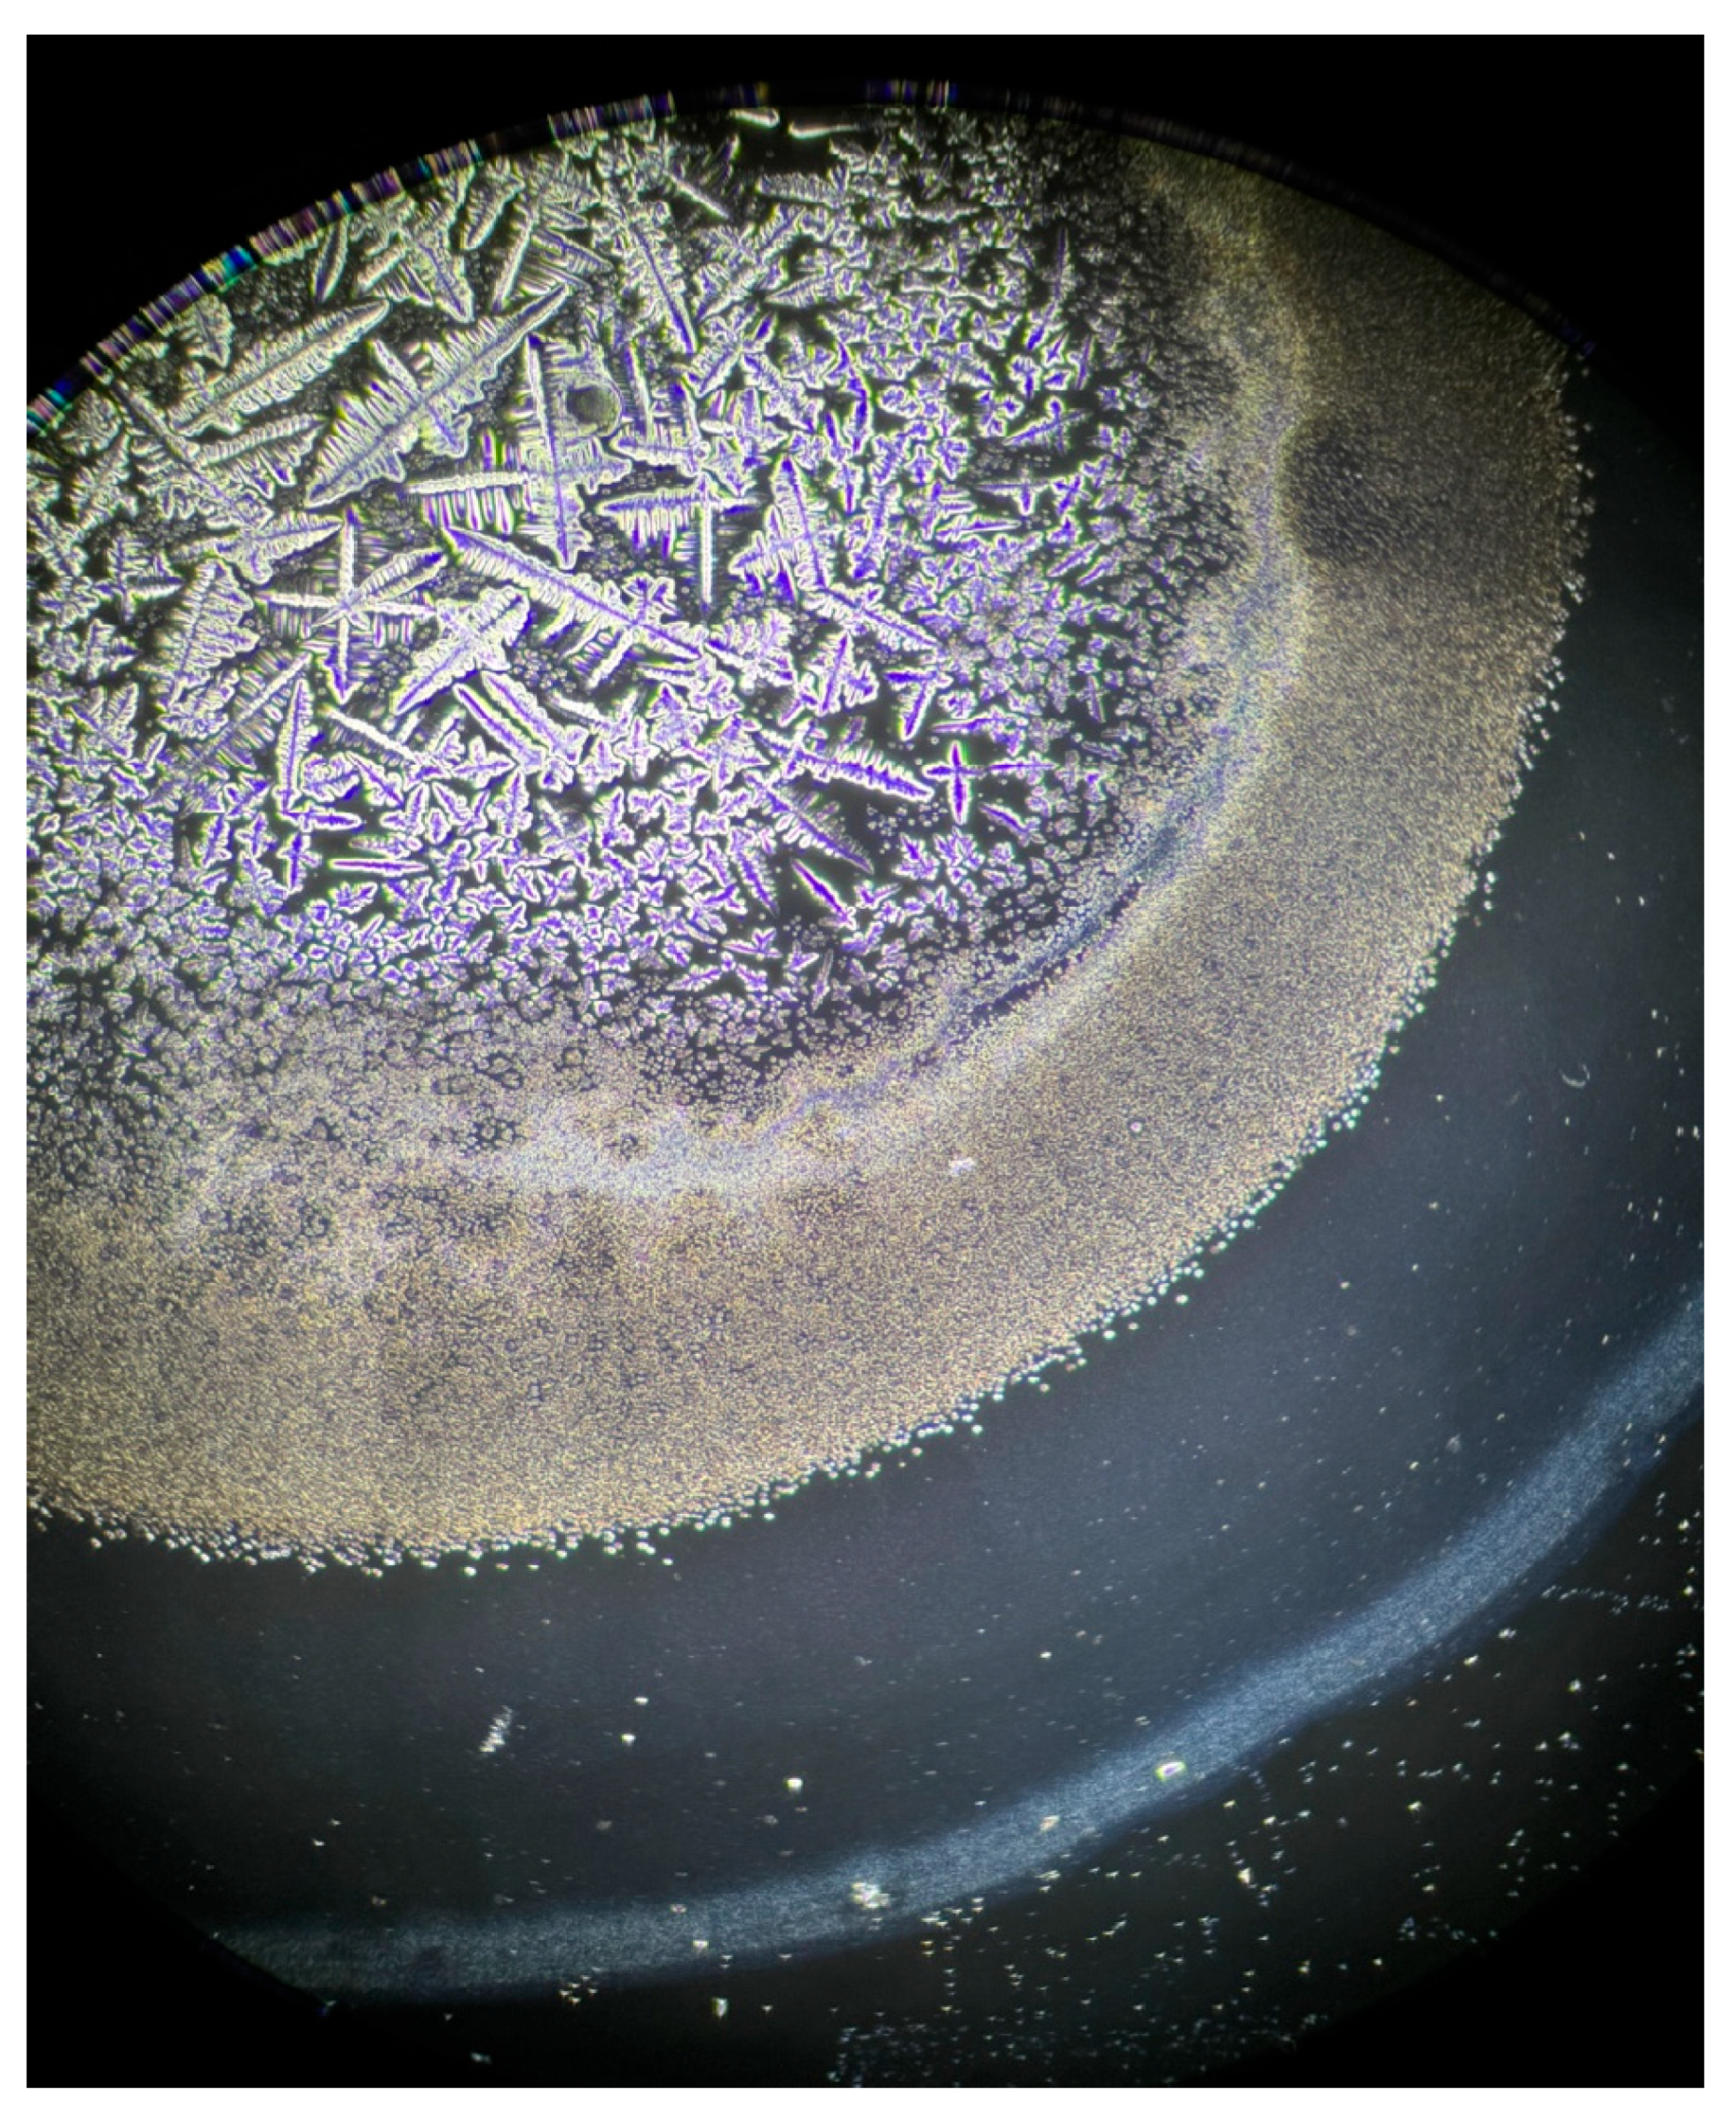

- López Solís, R.; Traipe Castro, L.; Salinas Toro, D.; Srur, M.; Toledo Araya, H. Microdesiccates produced from normal human tears display four distinctive morphological components. Biol. Res. 2013, 46, 299–305. [Google Scholar] [CrossRef]

- Masmali, A.M.; Purslow, C.; Murphy, P.J. The tear ferning test: A simple clinical technique to evaluate the ocular tear film. Clin. Exp. Optom. 2014, 97, 399–406. [Google Scholar] [CrossRef] [PubMed]

- Rolando, M.; Baldi, F.; Zingirian, M. Effects of hyperosmolarity on tear mucus ferning. Fortschritte Der Ophthalmol. Z. Der Dtsch. Ophthalmol. Ges. 1986, 83, 644–646. [Google Scholar]